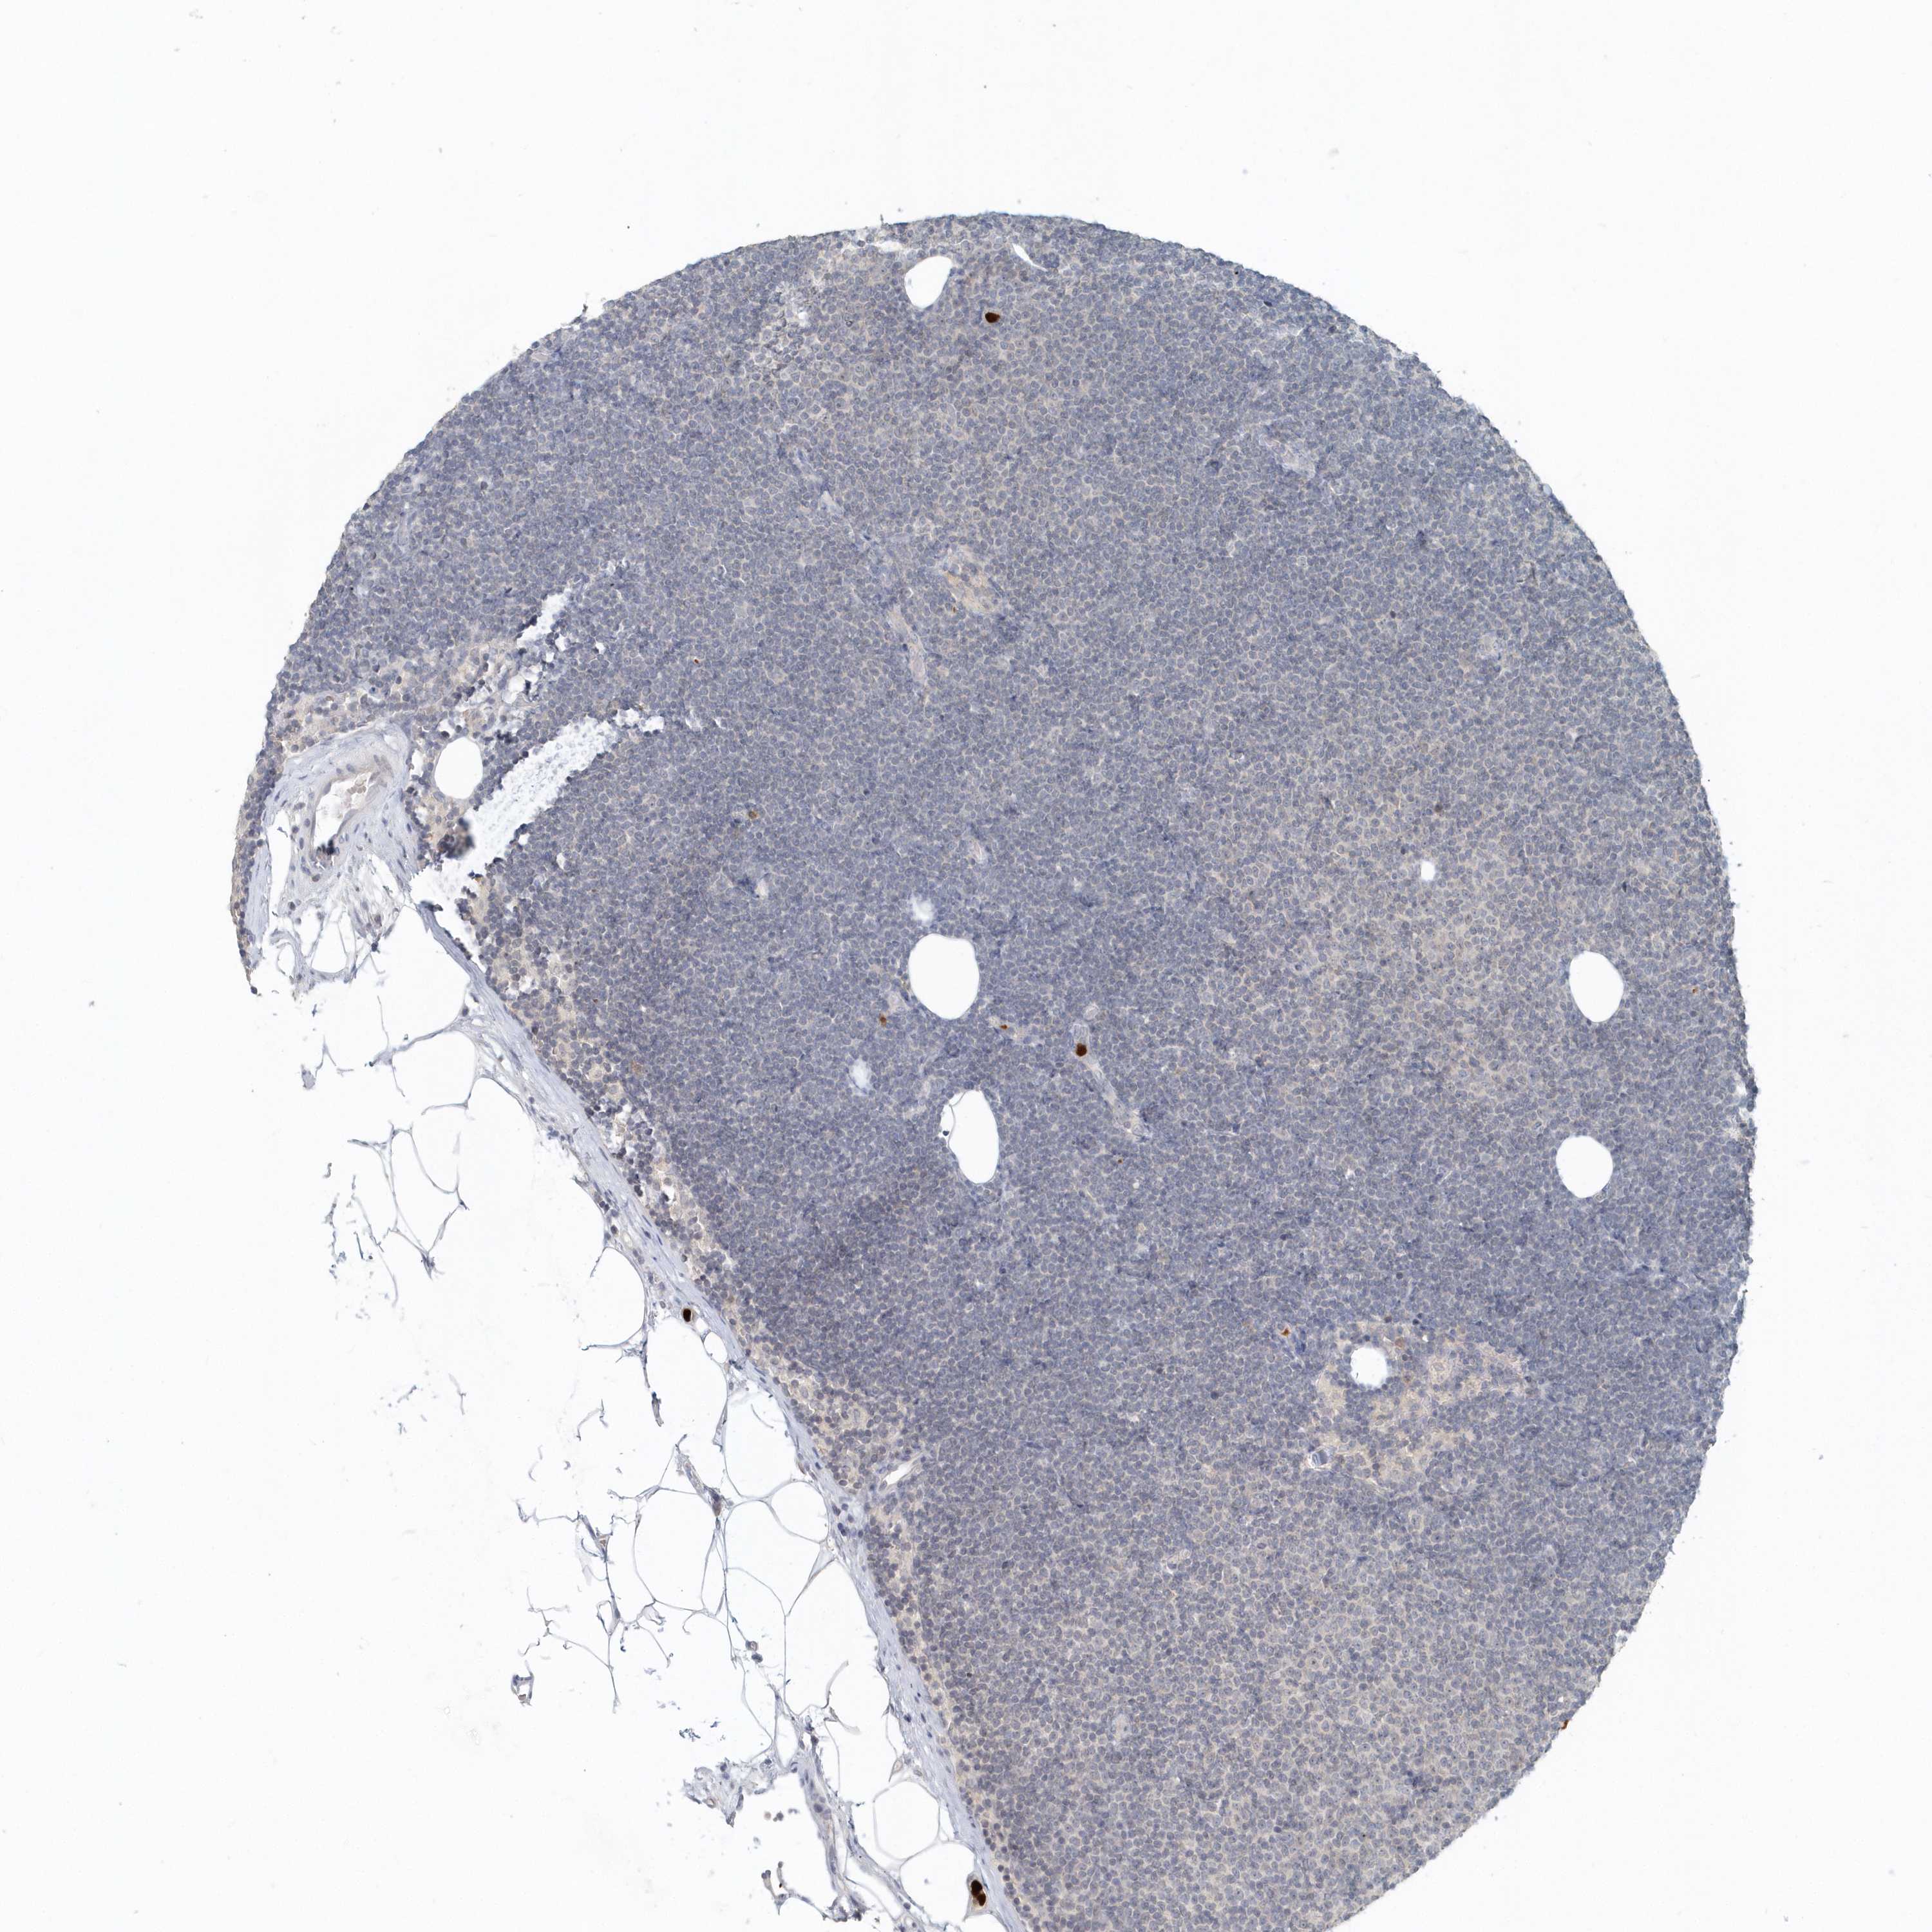

LYMPHOMA - Protein expressioni

A mouse-over function shows sample information and annotation data. Click on an image to view it in a full screen mode. Samples can be filtered based on level of antibody staining by selecting one or several of the following categories: high, medium, low and not detected. The assay and annotation is described here.

Antibody stainingi

Antibody staining in the annotated cell types in the current human tissue is reported as not detected, low, medium, or high, based on conventional immunohistochemistry profiling in selected tissues. This score is based on the combination of the staining intensity and fraction of stained cells.

Each image is clickable and will lead to virtual microscopy that enables deeper exploration of all samples and also displays staining intensity scores, fraction scores and subcellular localization as well as patient and tissue information for each sample.

Antibody HPA035929

Hodgkin's disease, NOS

Malignant lymphoma, non-Hodgkin's type, High grade

Malignant lymphoma, non-Hodgkin's type, Low grade